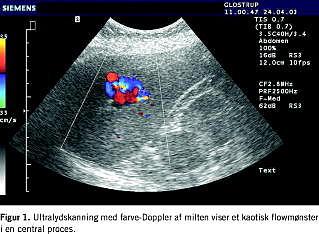

En 53-årig kvinde blev indlagt efter et fald på cykel, hvor hun slog hovedet og venstre side af kroppen. Patienten var kommotioneret, men var hæmodynamisk stabil, fraset et kortvarigt blodtryksfald. Hun havde pådraget sig fraktur af venstre os zygomaticus og ekskoriationer på de venstresidige ekstremiteter. Hun havde smerter i nedre venstre thoraxhalvdel, under venstre kurvatur og var øm i venstre nyreloge. Urinstiks viste hæmaturi kendt fra tidligere pga. nyresten. Hæmoglobin var på 10,1 mM. UL viste centralt i milten et afrundet ekkorigt område på ca. 3 cm, der kunne være et hæmatom. Subhepatisk fandtes en væskebræmme på op til 1 cm. På femtedagen fandtes der et fald i hæmoglobin til 8,1 mM. Patienten var fortsat hæmodynamisk stabil og upåvirket, fraset diffuse øvre venstresidige abdominalsmerter. Fornyet UL viste uændrede forhold. Patienten blev udskrevet i velbefindende en uge efter ulykken. Ved UL to uger senere fandtes nu en ekkofattig proces centralt i milten med et kaotisk Doppler-billede. Dette kunne være et pseudoaneurisme (Figur 1 ). Der var ingen fri væske i abdomen. Ved en arteriografi bekræftedes diagnosen. Ved efterfølgende embolisering var det ikke muligt at komme ud i forsyningsarterien, hvorfor der blev lagt fire coils umiddelbart før og efter afgangen af arterien. En kontrolarteriografi viste, at aneurismet var lukket, og at der var tilkommet et mindre miltinfarkt. Arteriografi og embolisering blev foretaget på et andet sygehus. Kontrol med UL og farve-Doppler seks uger senere viste et ekkofattigt område uden flow på ca. 1,5 cm. ved det tidligere aneurisme. De fire coils sås som en ekkorig trådlignende struktur, og man fandt følger efter et miltinfarkt.

Hyppig billeddiagnostisk kontrol er vigtig hos de patienter med miltlæsioner, som man vælger at behandle konservativt, idet der hos 70% af disse patienter ses miltruptur inden for de første to uger efter traumet [2]. Ved UL med farve-Doppler diagnosticeres et pseudoaneurisme i milten som et ekkofattigt område med turbulent arterielt flow [3]. Dette er en relativ billig, ufarlig og reproducerbar teknik, der muliggør hyppige kontroller. Alternativt benyttes CT, hvor korrekt timing af kontrastinjektionen er afgørende. Ved denne undersøgelse vil et kontrast-blush give mistanke om pseudoaneurisme. Et kontrast-blush ses som et velafgrænset, hyperdenst område efter kontrastinjektion [4]. MR-skanning benyttes sjældent, især af kapacitetsmæssige årsager.